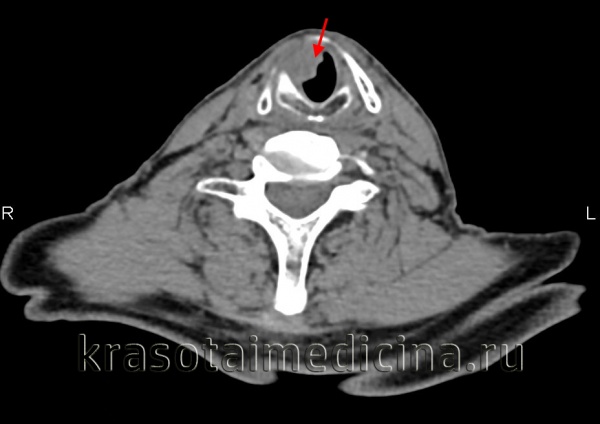

- Компьютерная томография (КТ) дает возможность определить размеры опухоли и ее распространение по лимфатическим узлам и окружающим тканям;

Дополнительными методами в диагностике рака гортани являются исследования голосовой функции, позволяющие оценить подвижность голосовых связок, форму голосовой щели и пр. К ним относятся стробоскопия, электроглоттография, фонетография. Распространенность рака гортани оценивают при помощи рентгенографии и МСКТ гортани. Наличие метастазов в ткани шеи выявляют при помощи УЗИ. Для определения регионарного метастазирования производят биопсию лимфатического узла.

При постановке диагноза учитывают результаты КТ и МРТ гортаноглотки и УЗИ шеи. Решающую роль в выявлении рака гортаноглотки играют данные фиброфаринголарингоскопии. При проведении исследования специалист осуществляет визуальную оценку размера, локализации и структуры новообразования, а затем выполняет биопсию подозрительного участка. Окончательный диагноз выставляют онкологи на основании гистологического исследования.